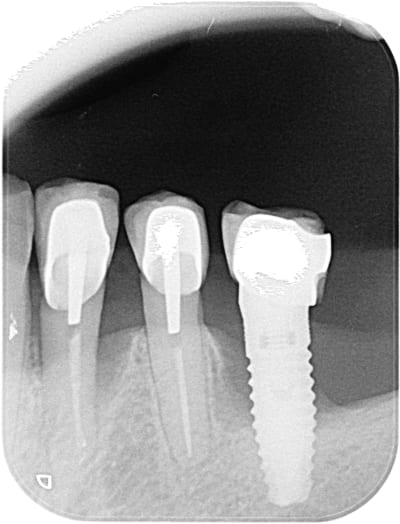

Bonjour quelqu'un saurait identifier l'implant 36 ?

J'aimerai le conserver avec une implantoplastie et une nouvelle couronne.

Voilà la radio !!

Ta radio est vraiment pas idéale pour deviner le type de connexion….

Ce qui se rapproche le plus c’est un TBR

https://www.spotimplant.com/fr/implants-dentaire/tbr/connect